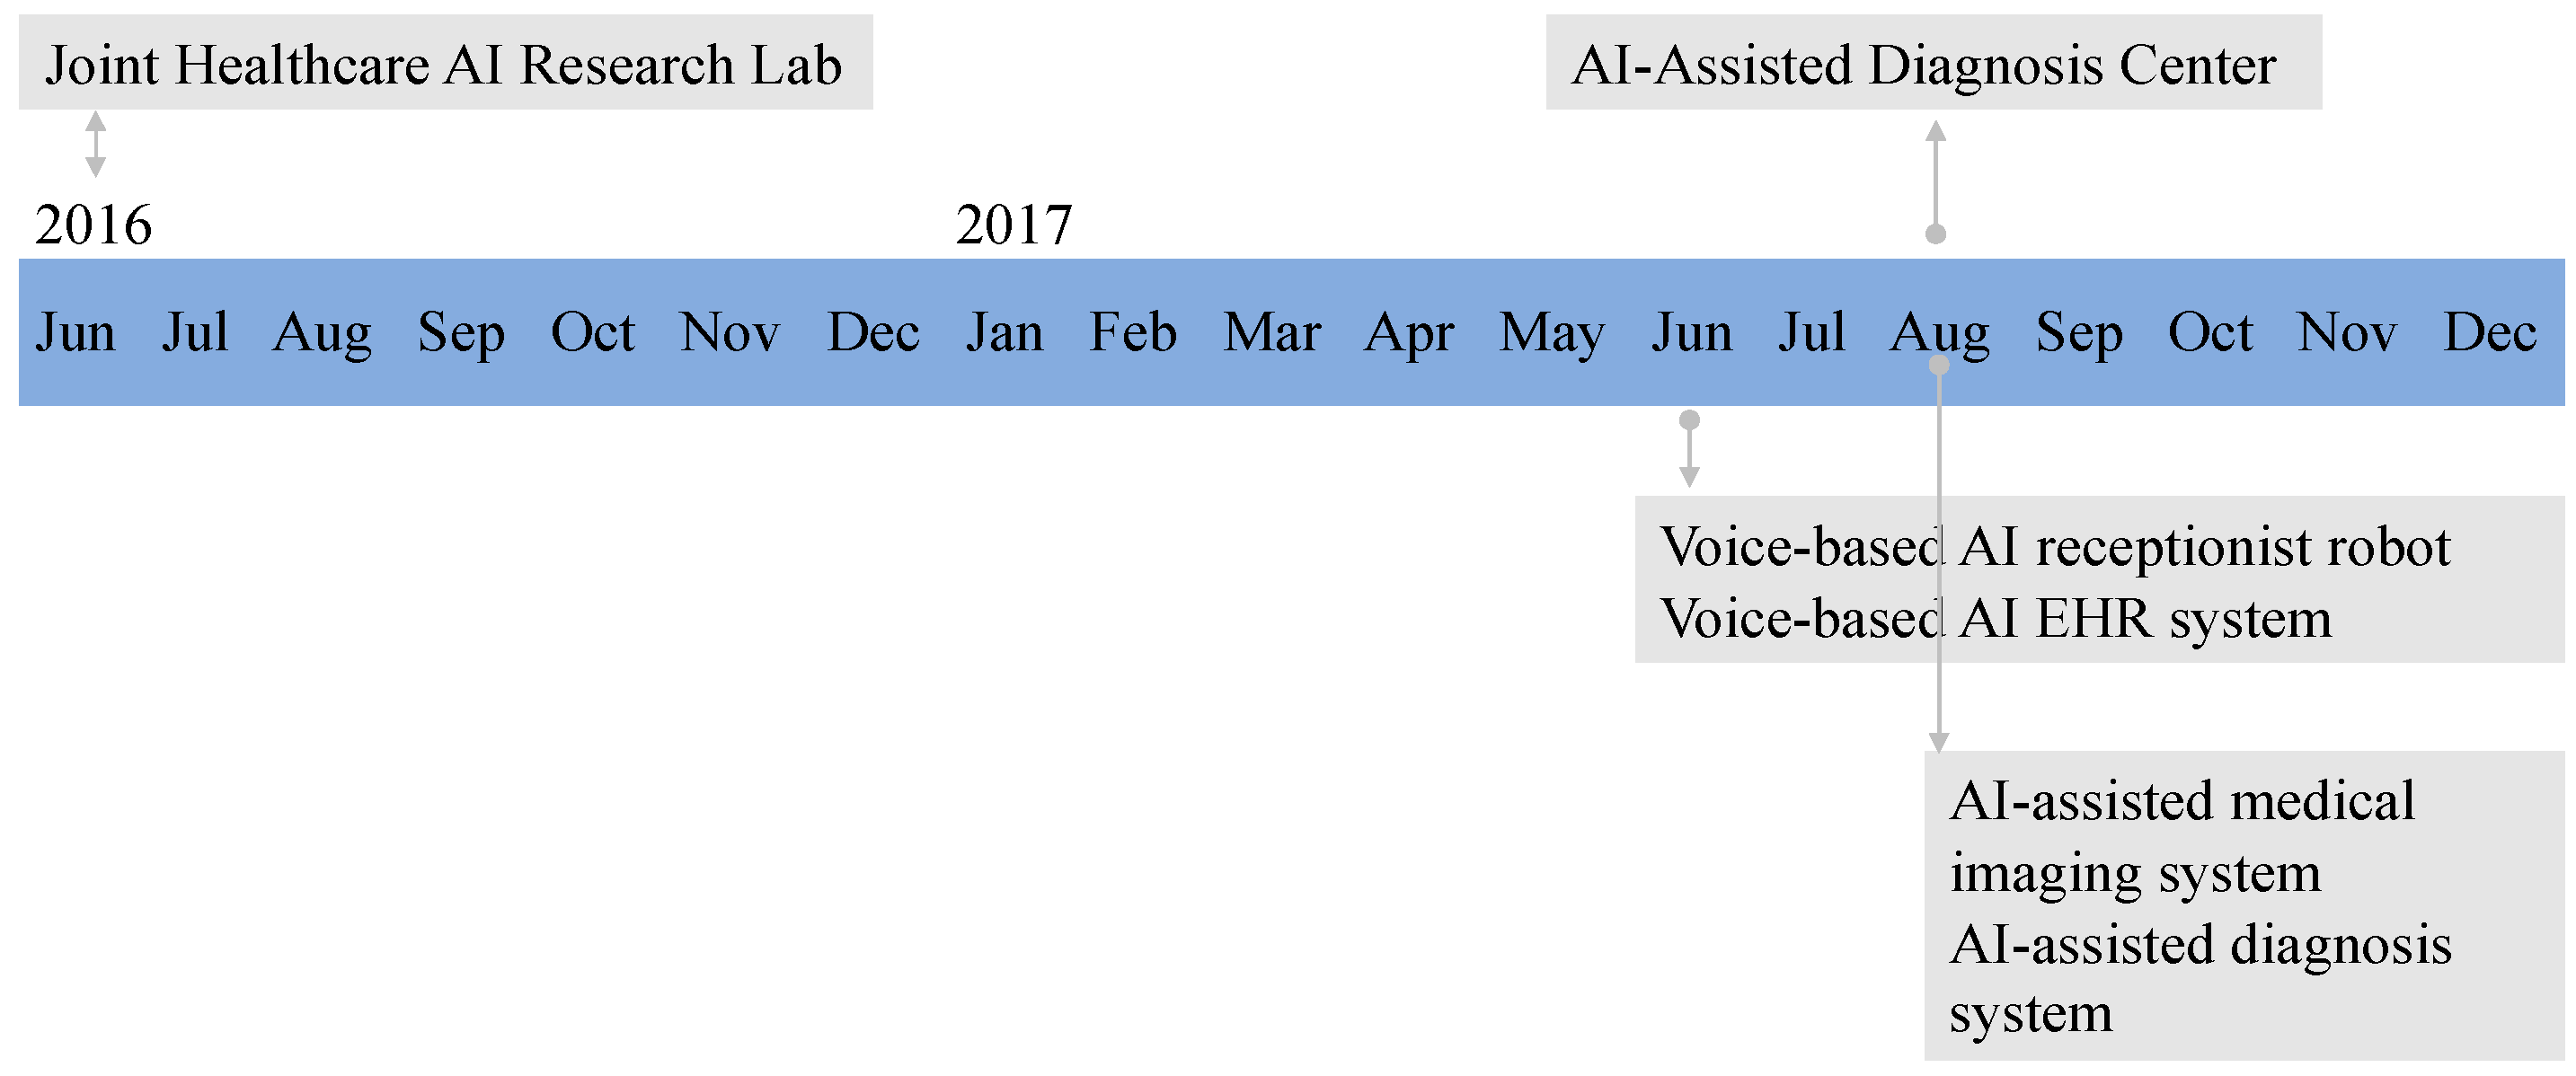

IJERPH, Free Full-Text